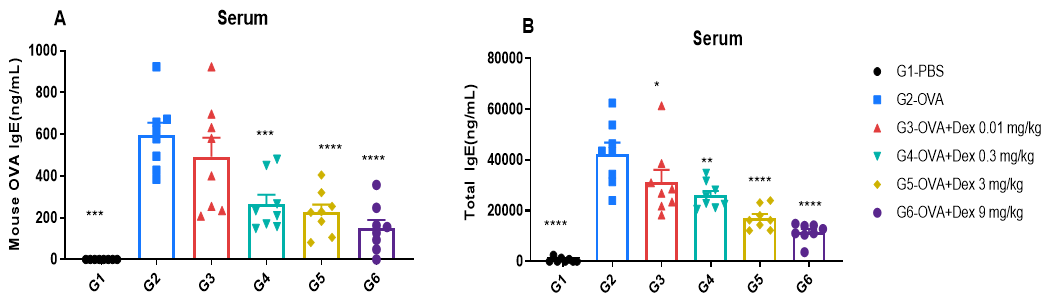

IgE Induction in Serum of Asthmatic Mice

ELISA-based detection of serum IgE in OVA-induced asthmatic mice.

Serum levels of OVA-specific IgE (A) and total IgE (B) were measured by ELISA. The G2 (OVA-only) group showed significantly elevated IgE levels compared to the G1 control group, confirming successful asthma induction. Dexamethasone treatment reduced OVA-specific and total IgE levels in a dose-dependent manner, supporting its immunosuppressive efficacy.